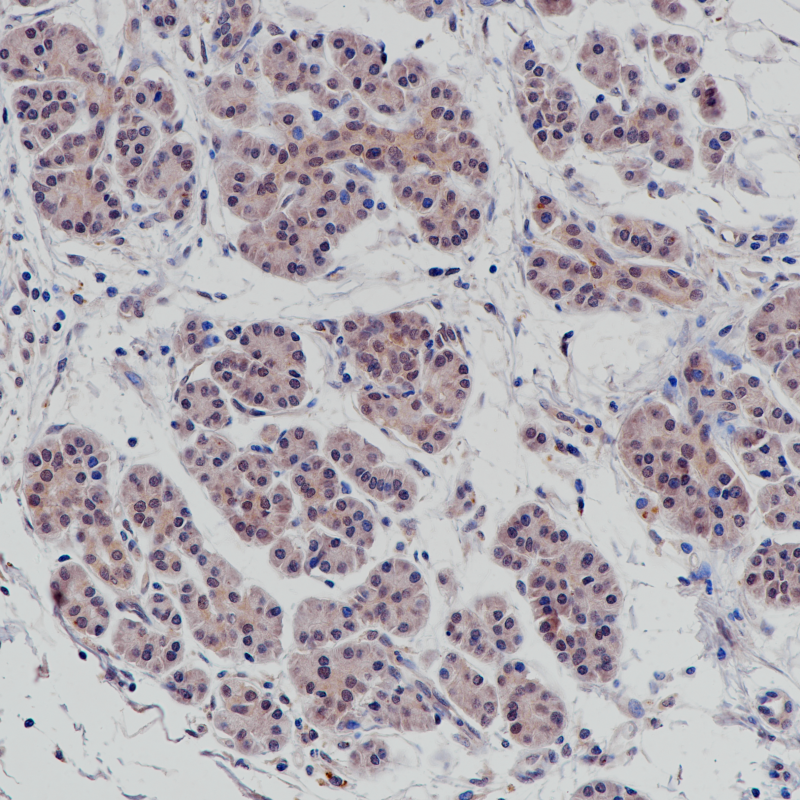

胰腺导管癌 正常表达部位SMAD4(BP6219)染色

SMAD 4与SMAD1和YY1在骨形态发生蛋白(BMP)介导的心脏特异性基因表达中起协同作用。它是在细胞核中形成的异质三聚体SMAD2-SMAD3-SMAD4复合物的组成部分,是TGF介导的信号通路所必需的,并促进SMAD2/SMAD4/FAST-1复合物与DNA的结合。SMAD 4在大多数组织中呈细胞质和核表达。SMAD 4基因的改变最初是在胰腺癌(导管腺癌)中发现的,但也出现在各种癌症中,如结直肠癌、胃癌、前列腺癌、黑色素瘤、头颈部癌和许多其他癌症中。

目录号

BX50242

克隆号

BP6219

阳性对照

胰腺导管癌

亚细胞定位

细胞核/细胞质